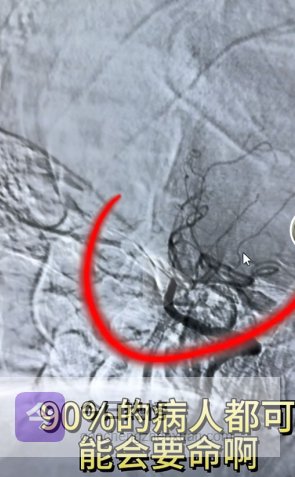

“36岁男子突发脑梗,陷入昏迷,诊断:基底动脉闭塞。”

一、基底动脉闭塞,为什么这么凶险?

这就是为什么基底动脉闭塞,被称为“最凶险的脑梗”。